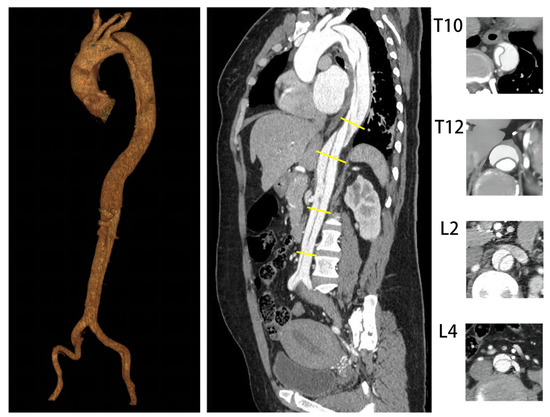

| Level of Aorta | Group | Before TEVAR | Follow-Up |

|---|---|---|---|

| Mean ± SD (mm) | Mean ± SD (mm) | ||

| T10 | Expanded group | 40.1 ± 4.2 | 44.0 ± 4.0 |

| Non-expanded group | 36.3 ± 3.8 | 36.1 ± 4.4 | |

| T12 | Expanded group | 35.8 ± 3.7 | 40.6 ± 5.3 |

| Non-expanded group | 34.4 ± 2.8 | 35.1 ± 3.2 | |

| L2 | Expanded group | 30.0 ± 3.3 | 32.5 ± 2.7 |

| Non-expanded group | 28.8 ± 2.4 | 29.3 ± 2.4 | |

| L4 | Expanded group | 27.5 ± 2.9 | 28.7 ± 3.0 |

| Non-expanded group | 24.2 ± 2.5 | 24.7 ± 2.7 |